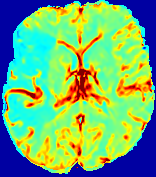

4.3.2 Diffusion Imaging via Advection-Diffusion

Slice #1Slice #2Slice #3Slice #4Slice #5Slice #6Dgtsuperscript𝐷gtD^{\text{gt}}Refer to captionRefer to captionRefer to captionRefer to captionRefer to captionRefer to captionDestsuperscript𝐷estD^{\text{est}}Refer to captionRefer to captionRefer to captionRefer to captionRefer to captionRefer to captionRefer to caption0.300.300.300.240.240.240.180.180.180.120.120.120.060.060.060.000.000.00(mm2/s)𝑚superscript𝑚2𝑠(mm^{2}/s)𝐕est𝟐subscriptnormsuperscript𝐕est2\|\bf{V}^{\text{est}}\|_{2}Refer to captionRefer to captionRefer to captionRefer to captionRefer to captionRefer to captionRefer to caption0.00300.00300.00300.00240.00240.00240.00180.00180.00180.00120.00120.00120.00060.00060.00060.00000.00000.0000(mm/s)𝑚𝑚𝑠(mm/s)

Figure 15: PIANO identifiability testing: diffusion imaging via advection-diffusion. Top row shows Dgtsuperscript𝐷gtD^{\text{gt}} used for simulating ground truth pure diffusion. Rows below show the estimated Destsuperscript𝐷estD^{\text{est}} and 𝐕est2subscriptnormsuperscript𝐕est2\|{\bf{V}}^{\text{est}}\|_{2} on corresponding slices. Note that the plotted value scale for 𝐕est2subscriptnormsuperscript𝐕est2\|{\bf{V}}^{\text{est}}\|_{2} is 0.01 of that for Dgtsuperscript𝐷gtD^{\text{gt}} and Destsuperscript𝐷estD^{\text{est}}.

Similarly, we test the behavior of PIANO when estimating both advection and diffusion from a pure diffusion-driven process. The goal is to determine if PIANO is able to recognize that there is only diffusion governing the given concentration time-series. We use the same ‘Diffusion Imaging’ data simulation of Sec. 4.2.1 as the concentration dataset, PIANO estimates both velocity 𝐕estsuperscript𝐕est{\bf{V}}^{\text{est}} and diffusivity Destsuperscript𝐷estD^{\text{est}}. Estimation results in Fig. 15 confirm PIANO’s identifiability again: the estimated 𝐕est2subscriptnormsuperscript𝐕est2\|{\bf{V}}^{\text{est}}\|_{2} is almost invisible compared to Destsuperscript𝐷estD^{\text{est}}, even plotted with a 1%percent11\% value range compared to that for Destsuperscript𝐷estD^{\text{est}}. On the other hand, Destsuperscript𝐷estD^{\text{est}} achieves comparable estimation performance as ‘Diffusion Imaging via Diffusion’ in which PIANO predicts Destsuperscript𝐷estD^{\text{est}} alone (shown in Fig. 13).